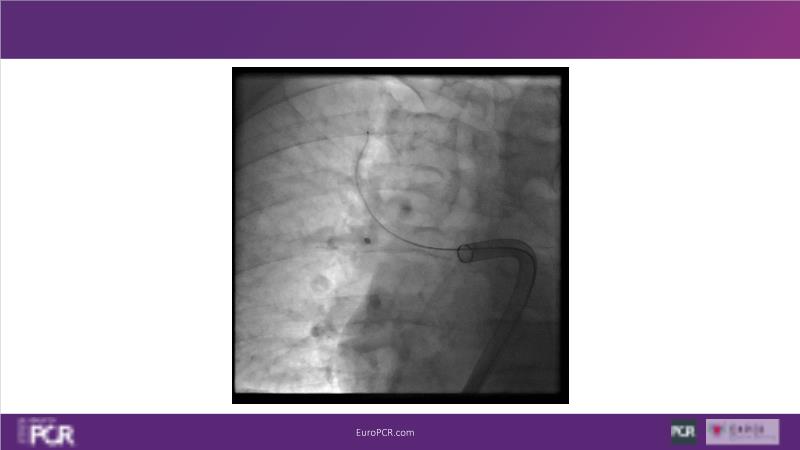

Why mechanical thrombectomy should be considered in the management of acute pulmonary embolism

In this EuroPCR 2024 session, study the case of a patient with high-risk pulmonary embolism and another with intermediate to high-risk pulmonary embolism, delve into discussions on clinical evidence for mechanical thrombectomy in pulmonary embolism, acquire skills to evaluate eligibility for mechanical thrombectomy, and learn how to integrate such technique in local pulmonary embolism patient pathway.